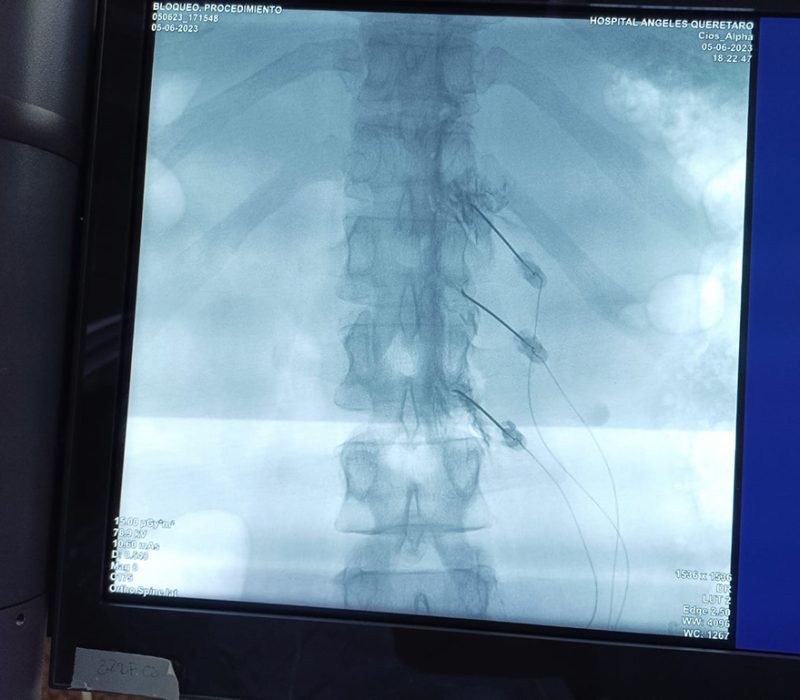

La ablación por radiofrecuencia (RFA), también llamada neurotomía por radiofrecuencia, utiliza ondas de radio para crear una corriente que en pocas palabras calienta una pequeña área de tejido nervioso. El calor destruye esa área del nervio, impidiendo que envíe señales de dolor al cerebro. La radiofrecuencia puede proporcionar un alivio duradero a las personas con dolor crónico, especialmente en la zona lumbar, el cuello y las articulaciones artríticas.

Durante un procedimiento de ablación por radiofrecuencia, se inserta una pequeña aguja guiada por imagen (fluoroscopia y/o ultrasonido) en el nervio objetivo que está causando el dolor, posteriormente se inserta un electrodo en la parte superior de la aguja, que envía ondas de radio a través de la aguja hasta el nervio objetivo. El calor provoca una lesión que impide que el nervio envíe señales de dolor al cerebro. Los nervios sanos cercanos no se dañan durante el procedimiento debido a que previo a realizar la lesión se realizan pruebas para estar seguros que únicamente se está realizando en el sitio deseado.